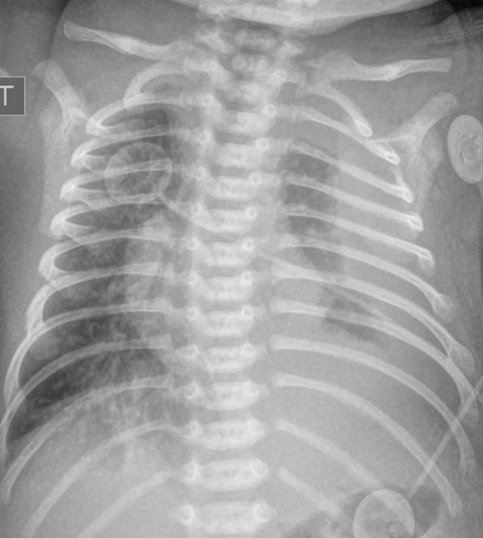

Chest x-ray: Demonstrated left-sided consolidation and pleural effusion( Fig-1) Subsequent chest CT revealed diffuse interstitial and septal thickening (Fig 2). She was admitted for management of worsening respiratory status, requiring chest tube placement and HFNC.

Chest radiographic findings include prominent interstitial markings, hyperinflation, ground-glass opacities especially in neonates, and pleural effusion. Chest CT may show diffuse or segmental interlobular septal thickening, perihilar infiltrates, ground-glass opacities, and hyperinflation (Fig 3). Pleural fluid analysis is consistent with chylous pleural effusion. Diagnostic criteria include a milky or opalescent appearance of the pleural fluid, elevated triglyceride levels(typically >110mg/dl), and lymphocyte predominance on cell count. In neonates and young infants who may not yet be enterally fed, triglyceride levels may be lower, therefore diagnosis may rely on lymphocyte predominance(>80%) and increase in triglyceride content following initiation of enteral feeds. These findings support impaired lymphatic drainage, as seen in congenital pulmonary lymphangiectasis. Lung biopsy with histology and immunochemical staining demonstrating dilated lymphatic channels and thickening of the interlobular septa and subpleural space is the gold standard for diagnosis. Immunohistochemical staining for endothelial cell markers CD31, CD34, and D2-40 confirms lymphatic origin. Echocardiogram should be performed to rule out pulmonary venous obstruction, such as hypoplastic left heart syndrome or TAPVR, which can cause secondary lymphangiectasia. Lymphangiograms have been used in some patients to evaluate thoracic duct disruption and lymphatic duct dilation. In our patient Echocardiogram showed large left pleural effusion, PFO with bidirectional flow, mild bilateral pulmonary artery stenoses, and normal biventricular systolic function.